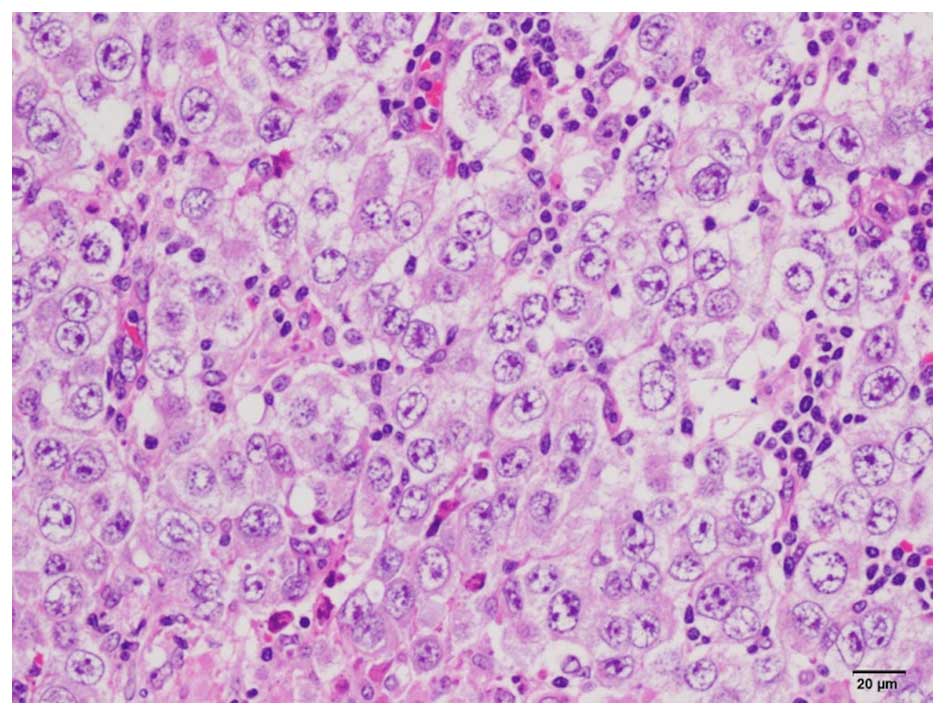

On histopathological examination, lymph node invasion was observed by semicircular tumor cells with large semicircular nuclei, and a ‘two-cell pattern’ (i.e., large tumor cells and small mature lymphocytes) was evident. The nucleus of the tumor cells contained 1–3 nucleoli (Fig. 4). On immunostaining, the tumor cells stained positive for C-kit and Oct3, but negative for Wilms' tumor-1 and α-inhibin; 60% of the tumor cells stained positive for Ki-67 (Fig. 5). The final diagnosis was dysgerminoma. In addition, normal follicles were found in the tumor tissue (Fig. 6); thus, the dysgerminoma was hypothesized to have developed from an ectopic ovary.

Figure 4.

On histological examination, lymph node invasion from semicircular tumor cells with large semicircular nuclei. Large tumor cells and small mature lymphocytes were observed.